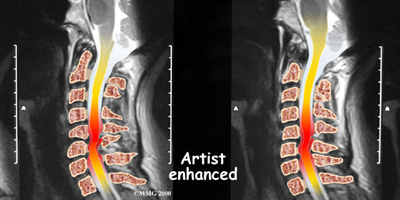

If more information is needed, your doctor may order an MRI. The MRI machine uses magnetic waves rather than x-rays to create pictures of the cervical spine in slices. MRIs show the cervical spine vertebrae, as well as the soft tissue structures, such as the discs, joints, and nerves. MRI scans are painless and don't require needles or dye. MRI scan has become the most common test to look at the cervical spine after x-rays have been taken.

DMX is a new fluoroscopic based x-ray system designed to objectively detect and document soft tissue/ligament injury most commonly associated with whiplash injuries of the spine. DMX evaluates biomechanical relationships and abnormal movements of the cervical spine. Specifically, DMX:

- Shows abnormal movement of vertebral bodies, facets, and other spinal elements

- Shows joint hypermobility, hypomobility, or restriction

- Shows normal or abnormal initiation of cervical motion

Example of DMX diagnostic video fluoroscopy.

DMX uses digital and optic technology now available. DMX is the latest generation of videofluoroscopy (VF) that uses low doses of radiation. The images have improved clarity and resolution over VF and are recorded digitally on CD or DVD disc. DMX digital images can be replayed and studied on standard computer systems. DMX images are simply x-ray images taken at 30 frames per second to form a multiple radiographic array or series that can be run as a movie file to display real time motion of the joints of the body.